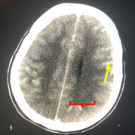

Mercedes Malone, MD; David Ritchie, MD; Peters Okonoboh, MD; Ahmed Ebrahim, MD

A 19-year-old woman presented to the hospital after she was discovered to be unresponsive by her family. The patient had a medical history of anxiety, depression, untreated pediculosis capitis of 1-year...